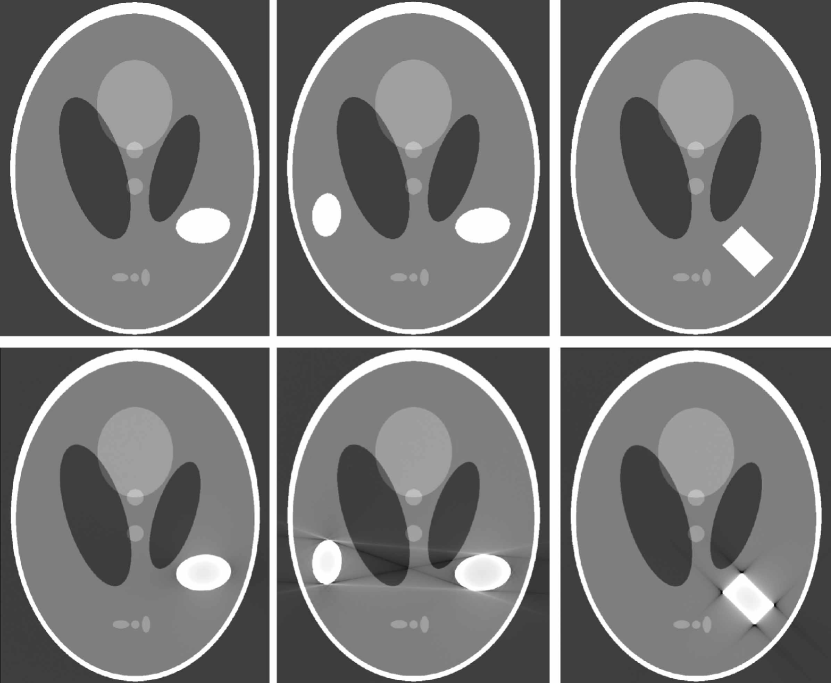

only when if the metal region D𝐷D is not strictly convex. In other words, the streaking artifacts in fCTsubscript𝑓CTf_{\mathrm{CT}} are related with the geometry of D𝐷D, as shown in Fig. 4. In the figure, we use the Shepp-Logan phantom as fE0subscript𝑓subscript𝐸0f_{E_{0}} and the homogeneous metallic objects χDsubscript𝜒𝐷\chi_{D} with the various geometries are added to illustrate the streaking artifacts in the reconstructed image fCTsubscript𝑓CTf_{\mathrm{CT}}.

Refer to caption

Figure 4: Illustration of streaking artifacts in the presence of metallic objects. First row and second row shows the Shepp-Logan phantom fE0subscript𝑓subscript𝐸0f_{E_{0}} with various metallic objects and the corresponding reconstructed fCTsubscript𝑓CTf_{\mathrm{CT}} (16) with the display window [-0.02 0.04], respectively.

From Theorem 3.1, fCTsubscript𝑓CTf_{\mathrm{CT}} does not have streaking artifacts. (See Fig. 4.) ∎